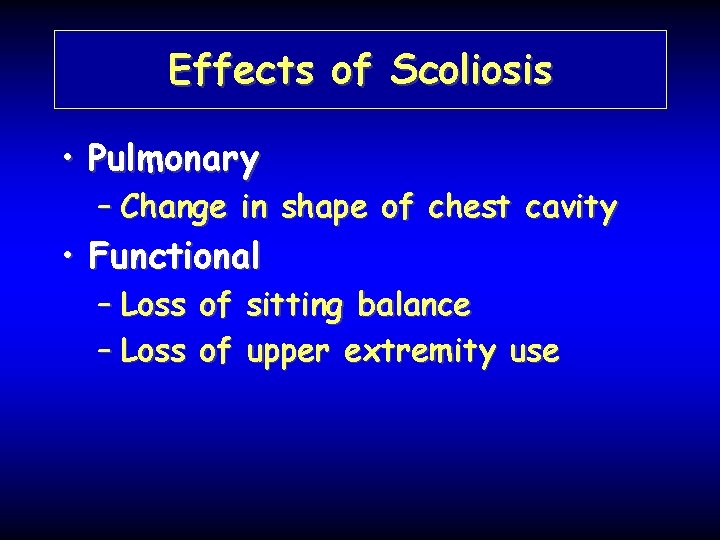

Effects of Scoliosis • Pulmonary – Change in shape of chest cavity • Functional – Loss of sitting balance – Loss of upper extremity use